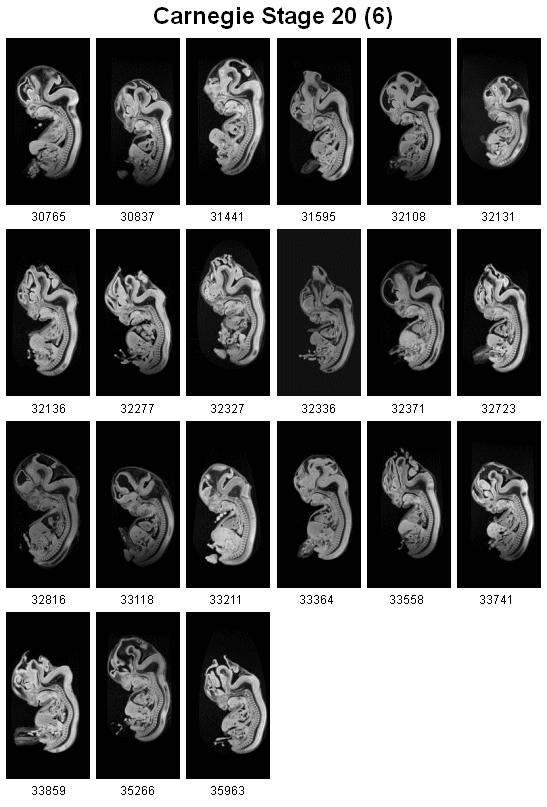

6th page